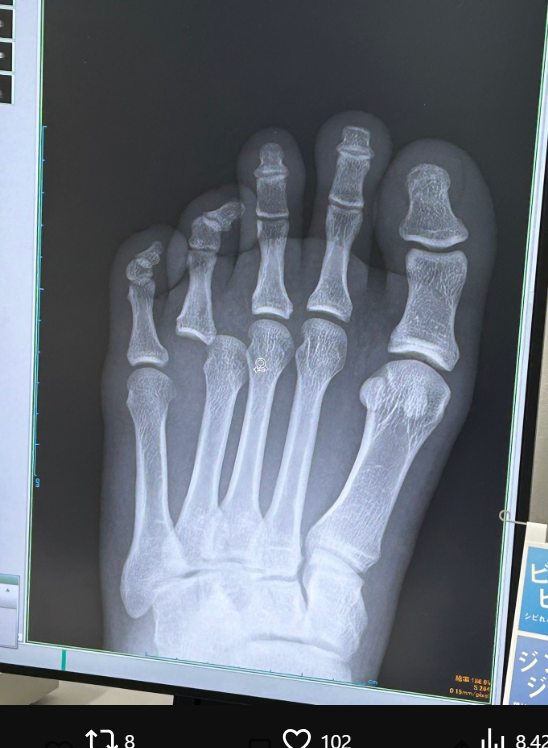

デンサヤームの左足のレントゲン写真。薬指の脱臼が分かる(@MisaKokubo)